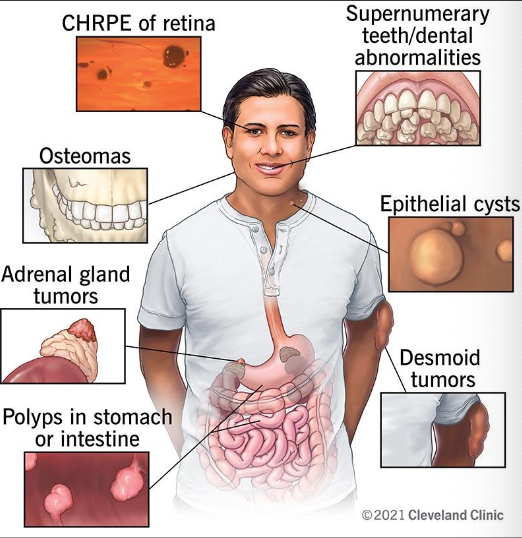

If you have multiple osteoma, what is that called?

Gardner syndrome

All of the following are part of Gardner syndrome EXCEPT

Cafe au lait spots

What is the mode of transmission for Gardner Syndrome?

Autosomal dominant; mutation chromosome #5 (APC)

What are the clinical features of Gardner Syndrome

Colorectal (adenoma) polyps which can become malignant (100% if not treated)

Multiple osteoma

Epidermoid cyst of skin

20% have supernumerary teeth

Thyroid carcinoma

Pigmented ocular fundus (90%)

Prognosis: guarded, close follow up

Epidermoid cyst of skin seen in

Gardner Syndrome

Epidermoid cyst of skin